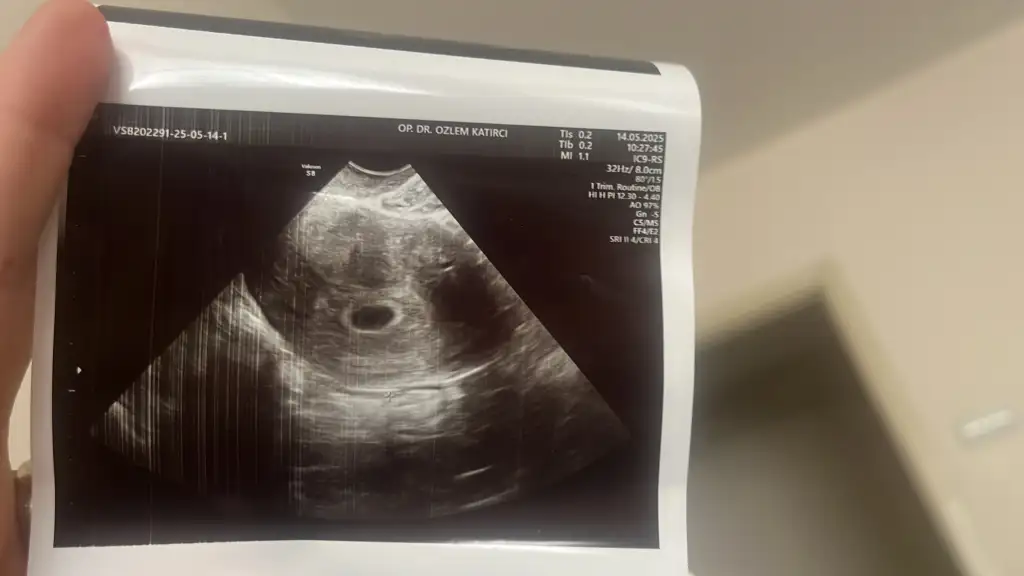

Merhaba çok şükür kısacık da olsa duyduk bugün kalp atışını ultrasonda 5+6 olarak ölçtü doktor gebelik haftasınıNe yaptınız randevunuz nasıl geçti umarım iyidir inşallah![]()

Valla çok anladığım bir şey değil ama benim ilk ultrasondaki kese fotoğrafım da bu şekildeydiAddete gıre 1 hafta gerıden gelmesı sıkıntı degıl yanı demı kuzum cok korkuyorum sence kesede yolk varmı doktorum soylemedı deEki Görüntüle 3591636

Gıttımmcanım çok sukur bebeısı gorduk kalp atısını duyduk 6 haftanın ıcındeymıs 4 5 gun adete gore ultrason gerıde ama sorun yokmus 1 ay sonra yenıden gel dedı doktor ıcım rahatladı goruncecanım gittin mi kontrole inşallah hayırlı mutlu bi haber almışsındır merak ettim![]()